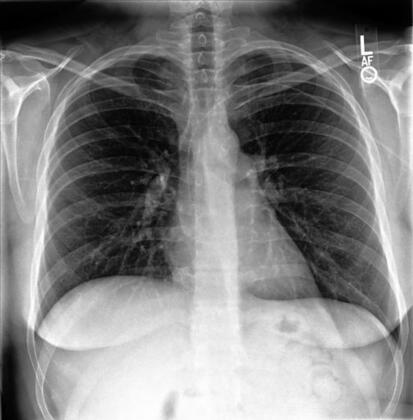

Chest X-rays may be divided into three principal types, according to the position and orientation of the patient relative to the X-ray source and detector panel: posteroanterior, anteroposterior, lateral. The posteroanterior (PA) and anteroposterior (AP) views are both considered as frontal, with the X-ray source positioned to the rear or front of the patient respectively. The AP image is typically acquired from patients in the supine position, while the patient is usually standing erect for the PA image acquisition. The lateral image is usually acquired in combination with a PA image, and projects the X-ray from one side of the patient to the other, typically from right to left. Examples of these image types are depicted in Figure 1.

Figure 1: Left: posterior-anterior (PA) view frontal chest radiograph. Middle: lateral chest radiograph. Right: Anterior-posterior (AP) view chest radiograph. All three CXRs are taken from the CheXpert dataset [131], patient 184.